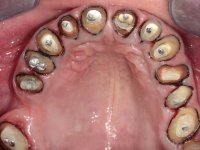

Paciente do sexo masculino, com 42 anos de idade, não fumador. Apresentava uma reabilitação metalo -cerâmica feita há mais de 10 anos com exposições radiculares e infiltrações. No maxilar superior apresentava uma coroa no 1.1,uma ponte de dois elementos no 2.1 e 2.2.e uma ponte de 4 elementos nos dentes 2.4,2.5,2.6 e 2.7 com o 2.6 como pôntico. Os dentes 1.6/1.5/1.4/1.3/1.2/1.1/2.1/2.2/2.3/2.4/2.5 e 2.7 apresentam tratamento endodôntico radical com o 2.4/2.5 e 2.7 a necessitarem de ser refeitos. No maxilar inferior apresentava uma ponte metalo-cerâmica de 4 elementos nos 4 incisivos e uma ponte de 3 elementos (3.3 e 3.4) com um dente supranumerário como pôntico. Os dentes 4.6/4.5 e 4.2 apresentavam tratamento endodôntico com o 4.2 a necessitar de ser refeito. Os dentes 4.3 e 4.4 apresentavam extensas cáries linguais com algum comprometimento mesial. As peças protéticas apresentavam-se infiltradas com exposição radicular associada. Apresentava uma D.V.O. diminuída e uma mordida cruzada lado direito. O paciente tinha uma satisfatória saúde periodontal e uma boa higiene oral.